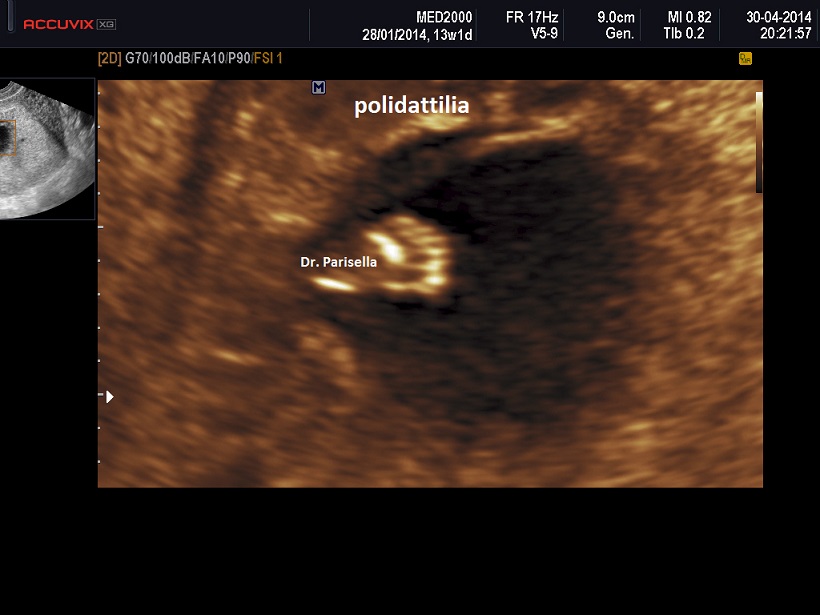

Sindrome di Werner - Sindrome ipoplasia della tibia-polidattilia - Nanismo Mesomelico di Werner   OMIM 188770

Segni principali:

ipoplasia tibia

polidattilia

pollice trifalangeo